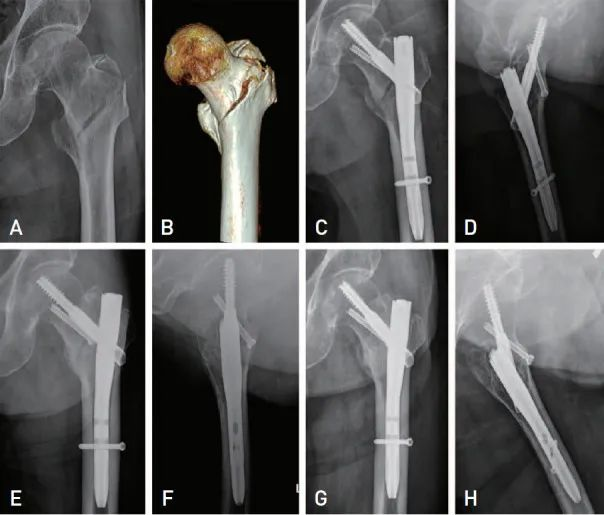

# كسور بين المدورين: تقنيات جديدة للمساعدة في إعادة الوضع وتقليل انزلاق مسمار رأس الفخذ تعتبر الجراحة العلاج الأساسي ل…